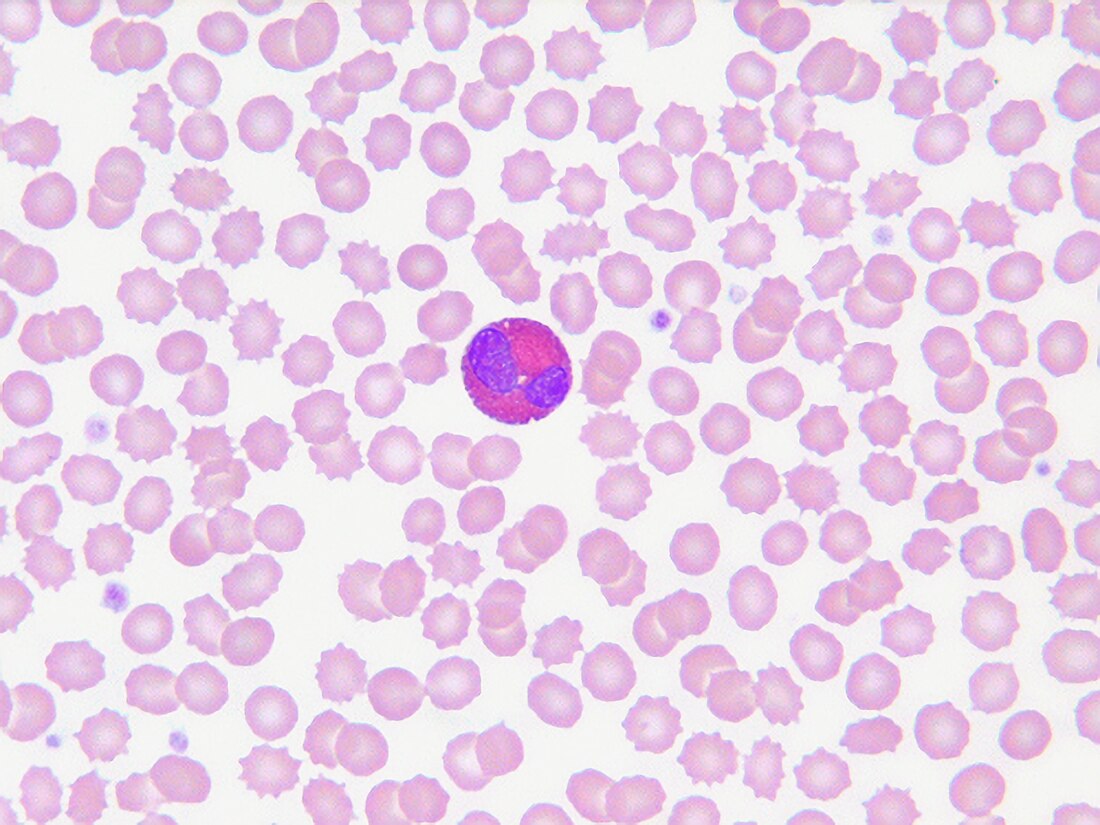

Peripheral Eosinophilia in a Confirmed Case of Canine Acute Eosinophilic Dermatitis with Edema (Wells-Like Syndrome)

image size: 923x1143